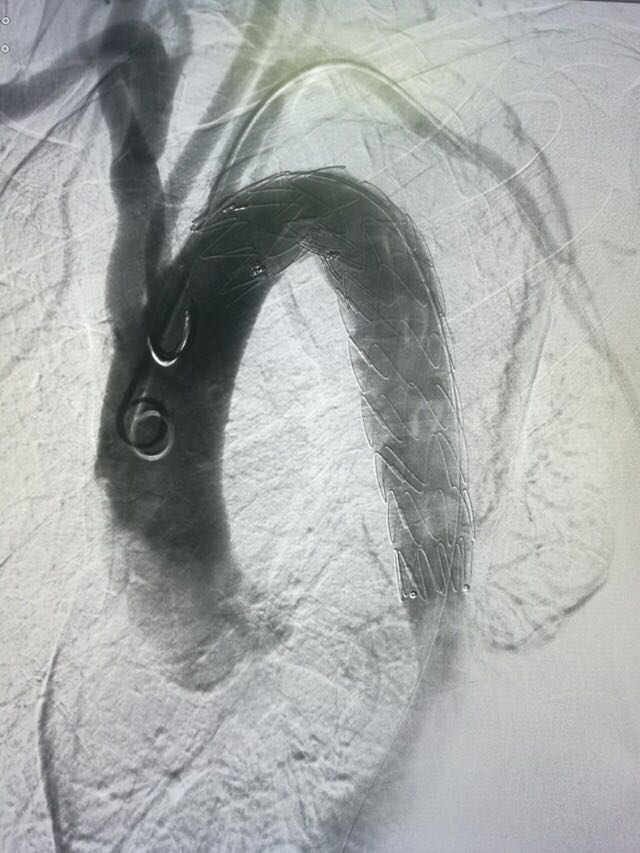

立即控制患者血压、心率,缓解疼痛,防止病情进展。采用微创手术方法,经右股总动脉穿刺入路,于胸主动脉夹层处释放 VAMF3030C200TE 覆膜支架,手术顺利。

VAMF3030C200TE 覆膜支架封闭主动脉夹层破口,且主动脉弓上动脉血流不受影响。